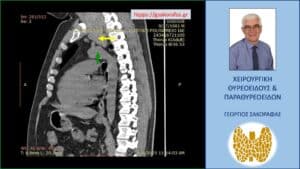

Αξονική τομογραφία – εικόνα σε διατομή κατά το προσθιοπίσθιο επίπεδο. Και στη διατομή αυτή φαίνεται η βαθιά κατάδυση του αριστερού λοβού (κίτρινο βέλος), που φθάνει στο άνω όριο του αορτικού τόξου (πράσινο βέλος).